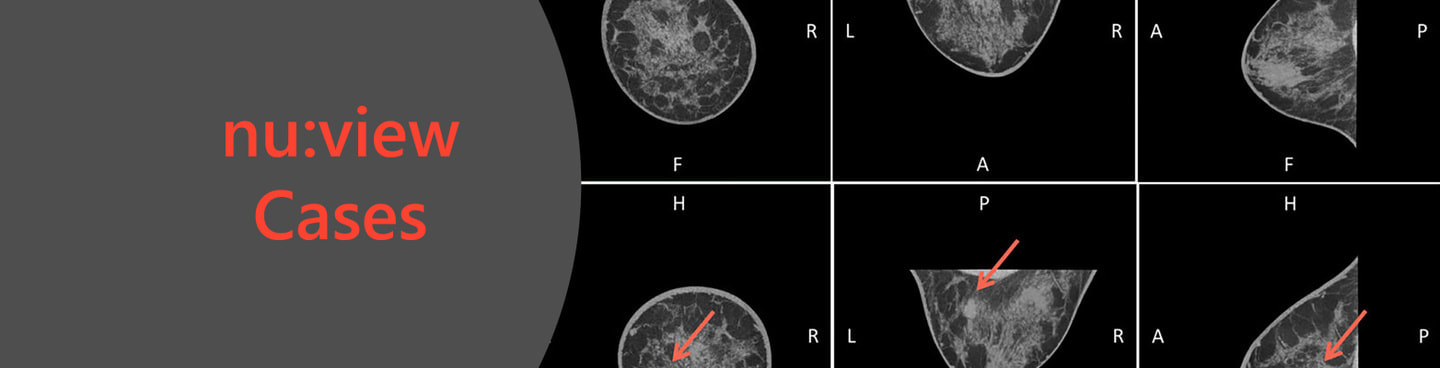

nu:viewの臨床症例

臨床画像はnu:viewの使用例です。

臨床症例